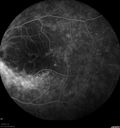

FLUORESCEIN ANGIOGRAPHY: Fluorescein angiography shows hyperfluorescence in a pattern consistent with retinitis pigmentosa variance, where there is sparing of the central macula with increased hyperfluorescence in the periphery.